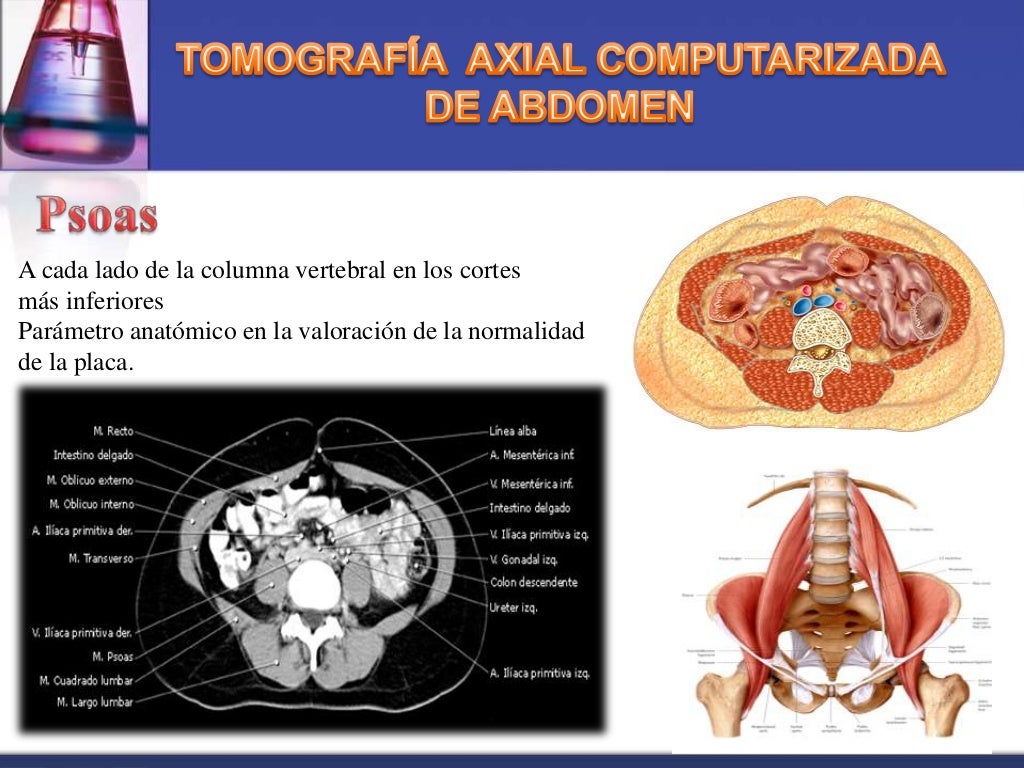

Tomografía abdominal que muestra zona de licuefacción y edema en la